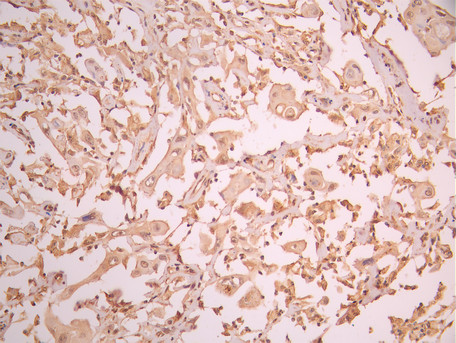

• IHC image of CSB-RA238916A0HU diluted at 1:100 and staining in paraffin-embedded human cervical cancer performed on a Leica BondTM system. After dewaxing and hydration, antigen retrieval was mediated by high pressure in a citrate buffer (pH 6.0). Section was blocked with 10% normal goat serum 30min at RT. Then primary antibody (1% BSA) was incubated at 4°C overnight. The primary is detected by a Goat anti-rabbit polymer IgG labeled by HRP and visualized using 0.05% DAB.